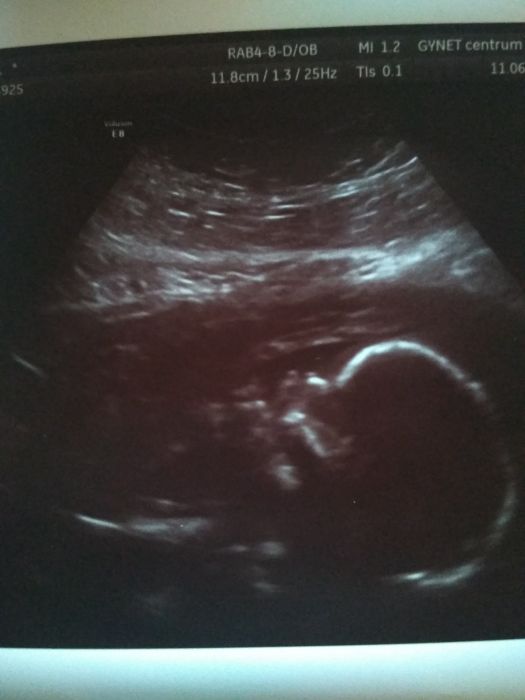

Tak dneska mám za sebou druhý screening.. krasne bylo vidět malé sice doktor si s ním povídal, že ukazuje jiné části než má.

jinak to vypadá na chlapečka.

Jinak krev mi nebrali, a trval skoro půl hodiny, zkontrolovali všechno mozek čelist, nos, rty, orgány..

A odpovídá 20 TT